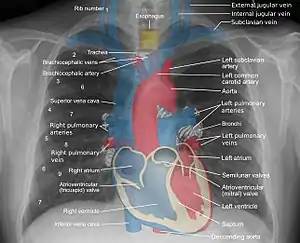

Mediastinal structures on a chest radiograph.

In the average person, the diaphragm should be intersected by the 5th to 7th anterior ribs at the mid-clavicular line, and 9 to 10 posterior ribs should be viewable on a normal PA inspiratory film. An increase in the number of viewable ribs implies hyperinflation, as can occur, for example, with obstructive lung disease or foreign body aspiration. A decrease implies hypoventilation, as can occur with restrictive lung disease, pleural effusions or atelectasis. Underexpansion can also cause interstitial markings due to parenchymal crowding, which can mimic the appearance of interstitial lung disease. Enlargement of the right descending pulmonary artery can indirectly reflect changes of pulmonary hypertension, with a size greater than 16 mm abnormal in men and 15 mm in women.[6]

Appropriate penetration of the film can be assessed by faint visualization of the thoracic spines and lung markings behind the heart. The right diaphragm is usually higher than the left, with the liver being situated beneath it in the abdomen. The minor fissure can sometimes be seen on the right as a thin horizontal line at the level of the fifth or sixth rib. Splaying of the carina can also suggest a tumor or process in the middle mediastinum or enlargement of the left atrium, with a normal angle of approximately 60 degrees. The right paratracheal stripe is also important to assess, as it can reflect a process in the posterior mediastinum, in particular the spine or paraspinal soft tissues; normally it should measure 3 mm or less. The left paratracheal stripe is more variable and only seen in 25% of normal patients on posteroanterior views.[7]

Localization of lesions or inflammatory and infectious processes can be difficult to discern on chest radiograph, but can be inferenced by silhouetting and the hilum overlay sign with adjacent structures. If either hemidiaphragm is blurred, for example, this suggests the lesion to be from the corresponding lower lobe. If the right heart border is blurred, than the pathology is likely in the right middle lobe, though a cavum deformity can also blur the right heard border due to indentation of the adjacent sternum. If the left heart border is blurred, this implies a process at the lingula.[8]